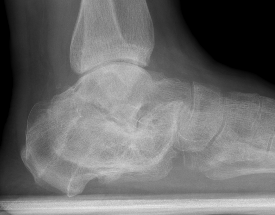

Osteoarthritis

- RCT of 309 displaced intra-articular fractures

- operative v non operative management with 2 year follow up

- STJ arthrodesis: non operative 17%, operative 3%

Calcaneal Malunion

Issues

Varus hindfoot - locks midfoot

Peroneal impingement

Shoewear problems